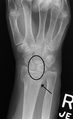

Scapholunate ligament disruption associated with a colles fracture